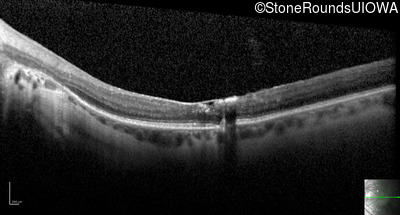

Optical Coherence Tomography - Left - 20/40 +1

Exemplar / OCT Stack

OCT Stack